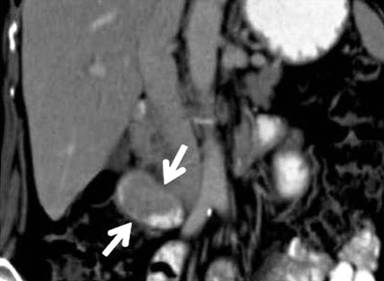

Computed tomography recognized a mass of the duodenum (Figure 1). However, magnetic resonance imaging did not reveal any lesion. Radiological differential diagnosis included gastrointestinal stromal tumor or adenoma. A magnetic resonance cholangiopancreatography was performed showing dilatation of the common bile duct (diameter equal to 9 mm) and gradually narrowing of its diameter downwards. Endoscopic retrograde cholangiopancreatography (ERCP) revealed a submucosal tumor located in the second portion of the duodenum. The lesion was seen as a large pedunculated polypoid mass originating from the second part of the duodenum in close proximity with the ampulla of Vater (Figures 2 and 3). No cholangiography was performed due to failure of cannulation of the bile duct. The pancreatic duct was normal without dilatation in its body or narrowing of its size. A sphincterotomy was performed 6 mm along the pancreatic sphincter, as it is considered an endoscopic therapy for chronic pancreatitis with papillary stenosis [8]. Two months after the procedure of sphincterotomy, the patient had another episode of acute pancreatitis without jaundice. Hence, the obstruction of the pancreatic duct due to the intermittent movements of the mass was considered as the cause of the episodes of acute pancreatitis. The patient was referred for surgical consultation and regional resection was decided. The operation was performed one month after the last episode of acute pancreatitis. Intraoperatively (Figure 4), there was no sign of lymph node metastases or local extension of the tumor.

Figure 1. Computed tomography obtained with oral and intravenous contrast material: coronal reformation image. An enhancing, well-marginated 5.5-cm soft-tissue intraluminal mass (arrows) is seen in the second portion of the duodenum extending to the ampullary region without obstruction. |